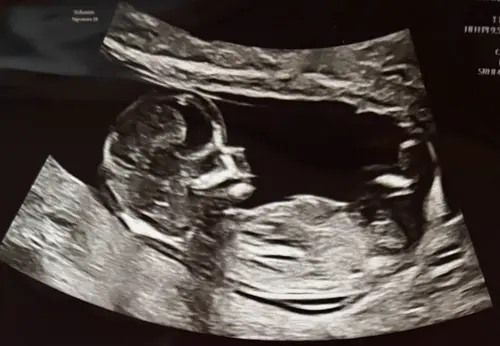

Ik heb deze vanmiddag geplaatst in het andere topic, is met 13+1. Ik heb 1 reactie ontvangen, zijn er nog mensen die een uitspraak kunnen/willen doen op basis van de nub? 🥰

Misschien helpt dit. De echopraktijk voor pretecho’s zegt bij deze echo een meisje omdat de nub vlak loopt aan het einde.